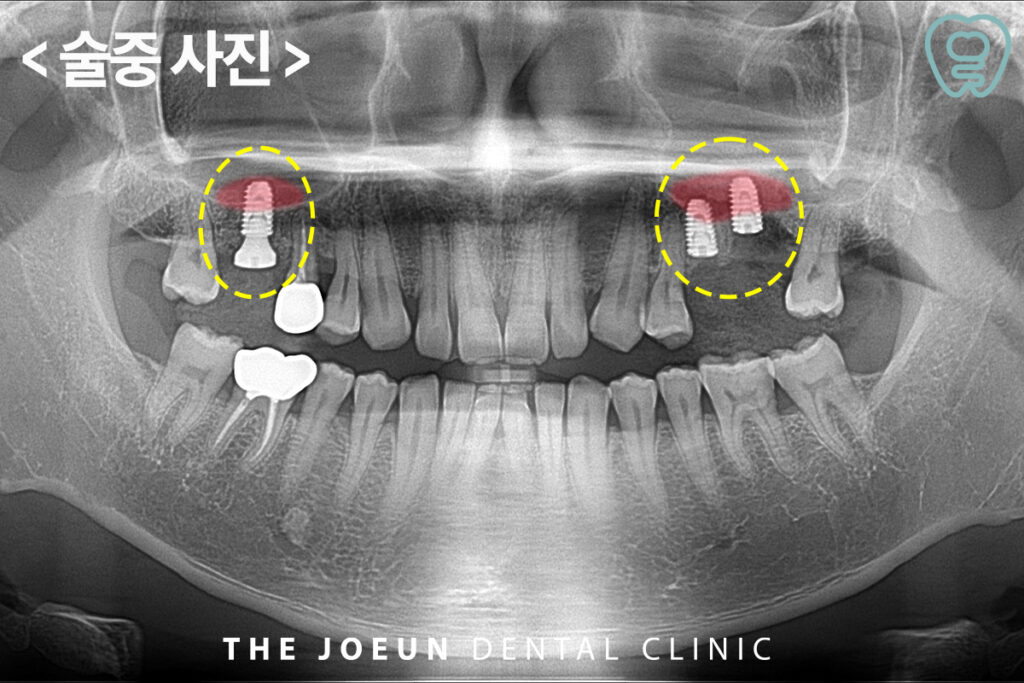

양쪽 모두 발치 후 임플란트 식립을 진행하였지만 아래로 많이 내려와 있는 상악동을 올려 뼈이식을 하는 상악동 거상술을 함께 진행하였습니다. 오른쪽은 치조정 접근법으로 진행하였고, 왼쪽은 측방 접근법으로 진행하였습니다.

상악동 거상술은 일반적으로 두가지 방식으로 나뉘는데 측방 접근법은 비교적 많은 양의 뼈이식이 필요한 경우에 활용되며, 잇몸 바깥쪽을 절개해 상악동 벽에 접근하는 방식이며 치조정 접근법은ㄴ 임플란트를 식립할 위치를 통해 직접 상악동을 거상하는 방법으로 뼈가 일정 수준 남아 있고 이식량이 많지 않은 경우 적용됩니다.